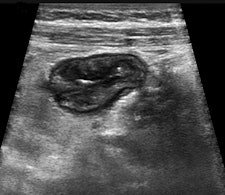

"Contrast agents are also beneficial in the resolution of an inflammatory mass as is frequently shown on imaging studies of those with IBD. While the grayscale features of abscess and phlegmon may be specific, there are many instances when this distinction cannot be made with conventional ultrasound alone. The injection of a microbubble contrast agent will show diffuse enhancement of an inflammatory phlegmonous mass, whereas an abscess will be avascular in the regions where there is pus," said Wilson, who will present on this topic during the opening day of the World Federation for Ultrasound in Medicine and Biology (WFUMB) congress, to be held in Vienna from 26 to 29 August.